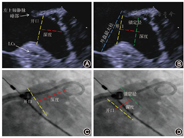

TEE指导或X线指导下完成房间隔穿刺,穿刺点靠下最重要,其次是靠后。TEE同时在主动脉短轴切面和双房切面指导穿刺针向下及向后穿刺卵圆窝;X线指导下向下、稍向后穿刺(图3)。完成房间隔穿刺后,静脉推注普通肝素100 U/kg,后每隔1 h追加1 000 U。

5.评估"PASS"原则(图4):Position(位置),器械最大直径平面正好或者稍远于并横跨左心耳开口;Anchor(锚定):通过牵拉确认封堵器固定好;Size(封堵器选型):封堵器实际展开最宽径相对于所选型号,应有一定的压缩;Sealing(封闭):保证所有的瓣叶都在器械远端并封闭,TEE测定封堵器残余分流≤ 5 mm[3,16]。

6.满足原则则释放封堵器。若不满足,则再回收以后重新定位释放,直至成功。(1) LAmbre封堵器评估"COST"原则:LCx:固定盘在LCx后面展开;Open(展开):固定盘充分展开,末端与连接在密封盘和固定盘之间的显影标志在一条直线上;Sealing(封闭):密封盘达到最佳封堵,TEE测定残余分流(peri-device leak, PDL) ≤ 3 mm[3,16];Tug test(牵拉):通过牵拉确认封堵器固定好(图5)。(2)ACP和Lacbes评估"CLOSE"原则:LCx:固定小叶展开后至少2/3要在LCx后面;Lobe(固定小叶):固定小叶要有一定压缩;Orientation(轴向):固定盘要与封堵器径线垂直;Separation(分离):固定盘和封堵盘要分离;Elliptical(椭圆形):封堵盘要有一定的形变(图6)。(3)Leftear评估"CODIS"原则:固定盘在LCx后面展开;固定盘充分展开(Open );封堵盘(Dish)要有一定的形变;通过牵拉确保固定牢靠(Insurance);密封盘达到最佳封堵(Sealing),TEE测定PDL ≤ 3 mm。